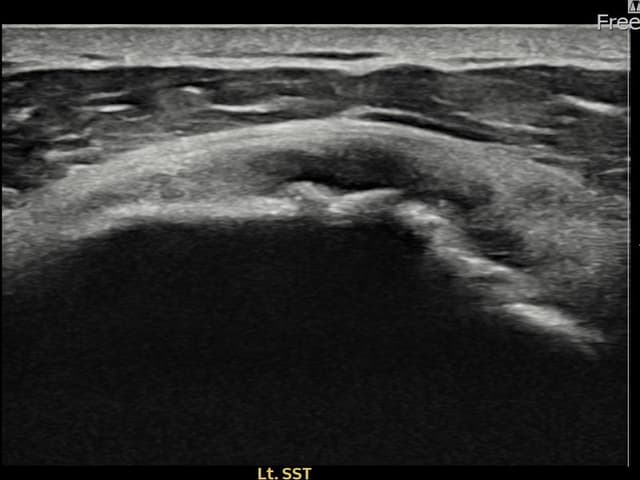

[촬영시기:23.07.18~23.09.14]

[어깨인대 축소봉합술] 좌측 어깨 광범위 파열로 수술을 권유받았으나 비수술 치료를 원해 내원하셨습니다.